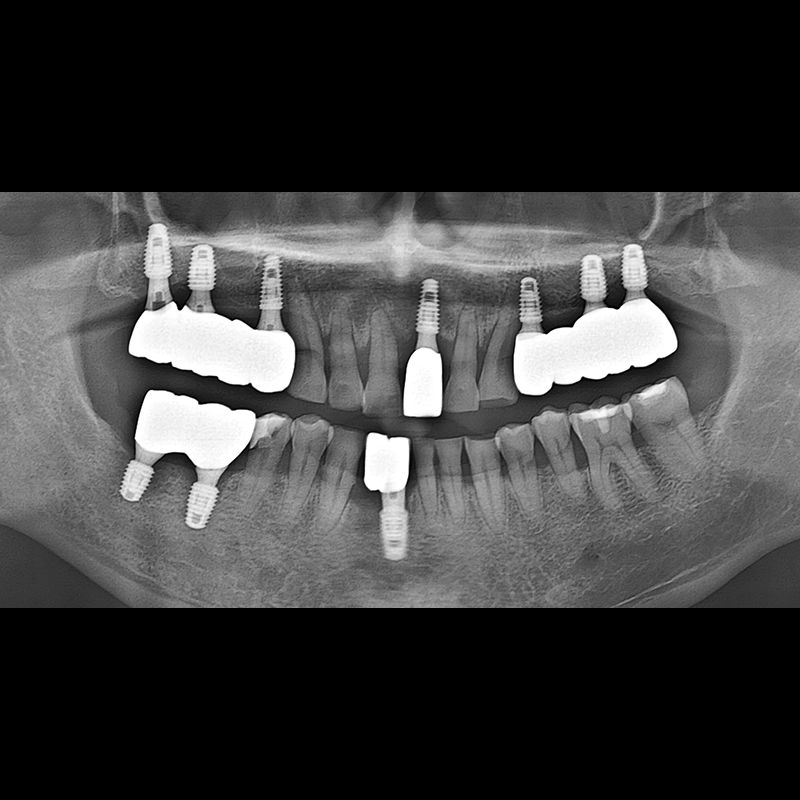

BEFORE AFTER

种植牙前后的照片 2025.05.30

在缺失的牙齿部分和难以挽救的牙齿位置植入了种植牙。